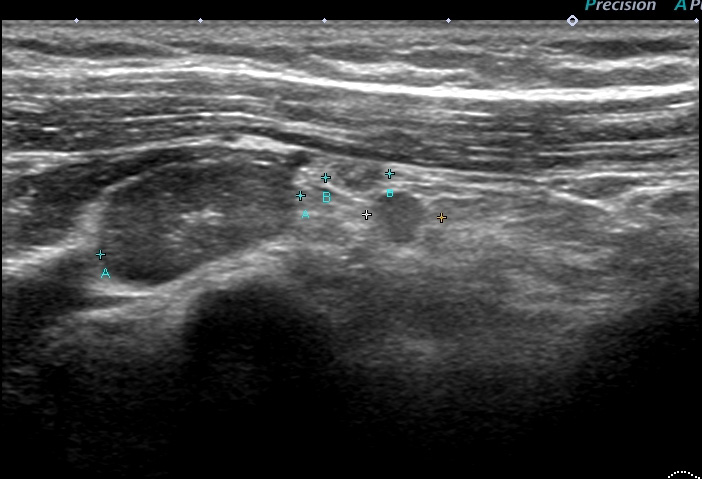

レベル2リンパ節 これが一番大きい 2㎝

大きなレベルⅡは、レベルⅢに近い部位までせり出し、その奥(図中央)にはレベルⅢが

確認できる。

大胸筋の外側にリンパ節2つ、大胸筋の裏にリンパ節1個 これら3個がレベルⅠ

小胸筋裏にリンパ節(これが最大で2㎝)これがレベルⅡ

それより内側(奥)に比較的小さいリンパ節2個 これらがレベルⅢ

色分けすると 赤とオレンジ:レベルⅠ、 黄色:レベルⅡ 、赤(周囲に点線の小さいもの):レベルⅢ

一番外側のリンパ節(レベル1)